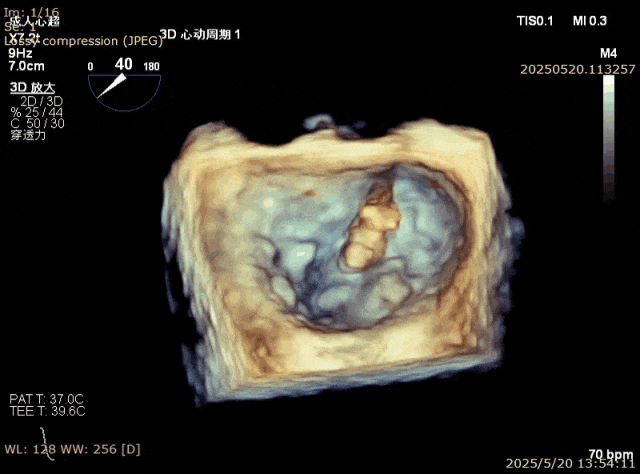

对于交界区病例,传统的做法是先夹合交界区,然后再夹合中央区。但是,对有些挑战病例,靠交界区瓣叶甩动严重,难以充分捕获瓣叶。这时候,可以反常规,先夹合靠中央区甩动不严重的瓣叶,限制了交界区瓣叶的甩动,再夹合交界区的瓣叶。这种情况下,交界区被第一个夹夹合后剩下一个小孔,进去输送系统难度较大,需要术者精细操作,避免将第一个夹子搅拌脱落。另外,该方法夹子几乎是有去无回,一旦进入后左心室后无法再撤出到心房,因此在心房侧就要把夹子和弹道调整到满意的状态,然后小心推送夹子通过小孔进入左心室内(图8-11)。但这种方法往往可以把交界区瓣叶夹合很大量,相对传统方法效果更好。

图8. 上一个病例,Barlow样改变,A3,P2, P3脱垂,靠内交界区甩动更严重

图9. 2.5区植入一枚夹子后,内交接残余脱垂

图10. 从小孔送入第二个夹子

图11. 最后结果满意